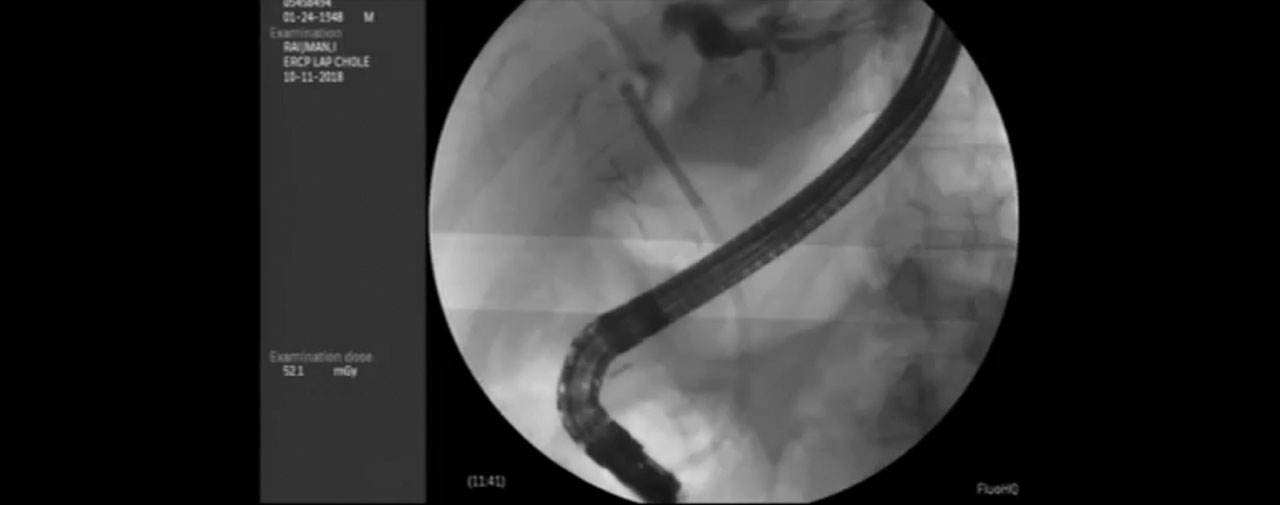

The patient underwent an ERCP, biliary sphincterotomy, and stone removal. At the time of surgery, cholangiograms were taken, which were read as normal. He continued to experience fever, weight loss and malaise, as well as persistent hyperbilirubinemia, elevated LFT’s and moderate RUQ pain. The patient was then referred to our hospital.

Initial Post-Cholecystectomy ERCP

An ERCP was then performed, at which time the patient had evidence of an incomplete sphincterotomy. In addition, a jagged 15mm stone was identified and large amounts of purulent bile extruded. Due to these observations, cholangioscopy was not performed and a 10Fr stent was placed. The patient’s symptoms resolved completely and he returned for definitive ERCP two months later.